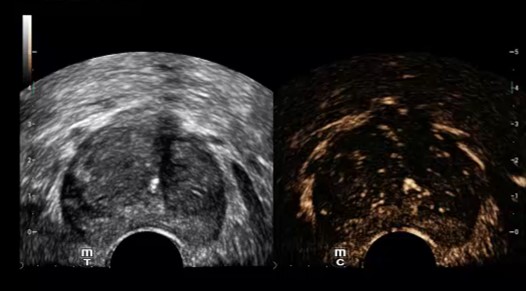

CEUS prostaty

Vyhodnotenie perfúzie mikrocirkulácie na diagnostiku rakoviny prostaty. Technológia UWN+, vysoká citlivosť, dlhá doby perfúzie.

UWN+ (Ultra-Wideband Non-linear) kontrastné zobrazenie - CEUS: Excelentná citlivosť na kontrastnú látku aj s minimálnym signálom. Dlhší perfúzny čas s nižším MI. Lepšia vizualizácia perfúzie v jemných cievach s MFE ( Micro Flow Enhancement ). Presná diagnostika benígnych a malígnych tumorov. Výrazne zvyšuje mieru detekcie drobných lézií.

UWN+ (Ultra-Wideband Non-linear) kontrastné zobrazenie - CEUS: Excelentná citlivosť na kontrastnú látku aj s minimálnym signálom. Dlhší perfúzny čas s nižším MI. Lepšia vizualizácia perfúzie v jemných cievach s MFE ( Micro Flow Enhancement ). Presná diagnostika benígnych a malígnych tumorov. Výrazne zvyšuje mieru detekcie drobných lézií.